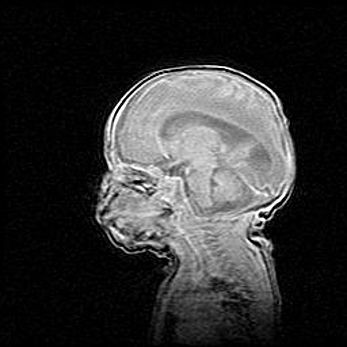

Неполная лизэнцефалия (пахигирия). Открытая гидроцефалия.

Возраст: 17 дней

Вес: 3110 г

Пол: мужской

Окружность головы: 33,5 см

Срок гестации: 35-36 недель

Лизэнцефалия—недоразвитие корковой пластинки и мозговых извилин в результате нарушения миграции нейронов коры. Поверхность мозговых полушарий гладкая. Микроскопически выявляется отсутствие нормальных слоев коры и скопление групп нейронов в подкорковом белом веществе.

Пахигирия—уменьшение числа вторичных извилин. В пораженном полушарии нервные клетки образуют толстый недифференцированный слой с неправильно расположенными нервными волокнами и группами гетеротопных клеток. Нервные клетки незрелые. Белое вещество истончено. При этом нередко аномально развит корково-спинномозговой путь.